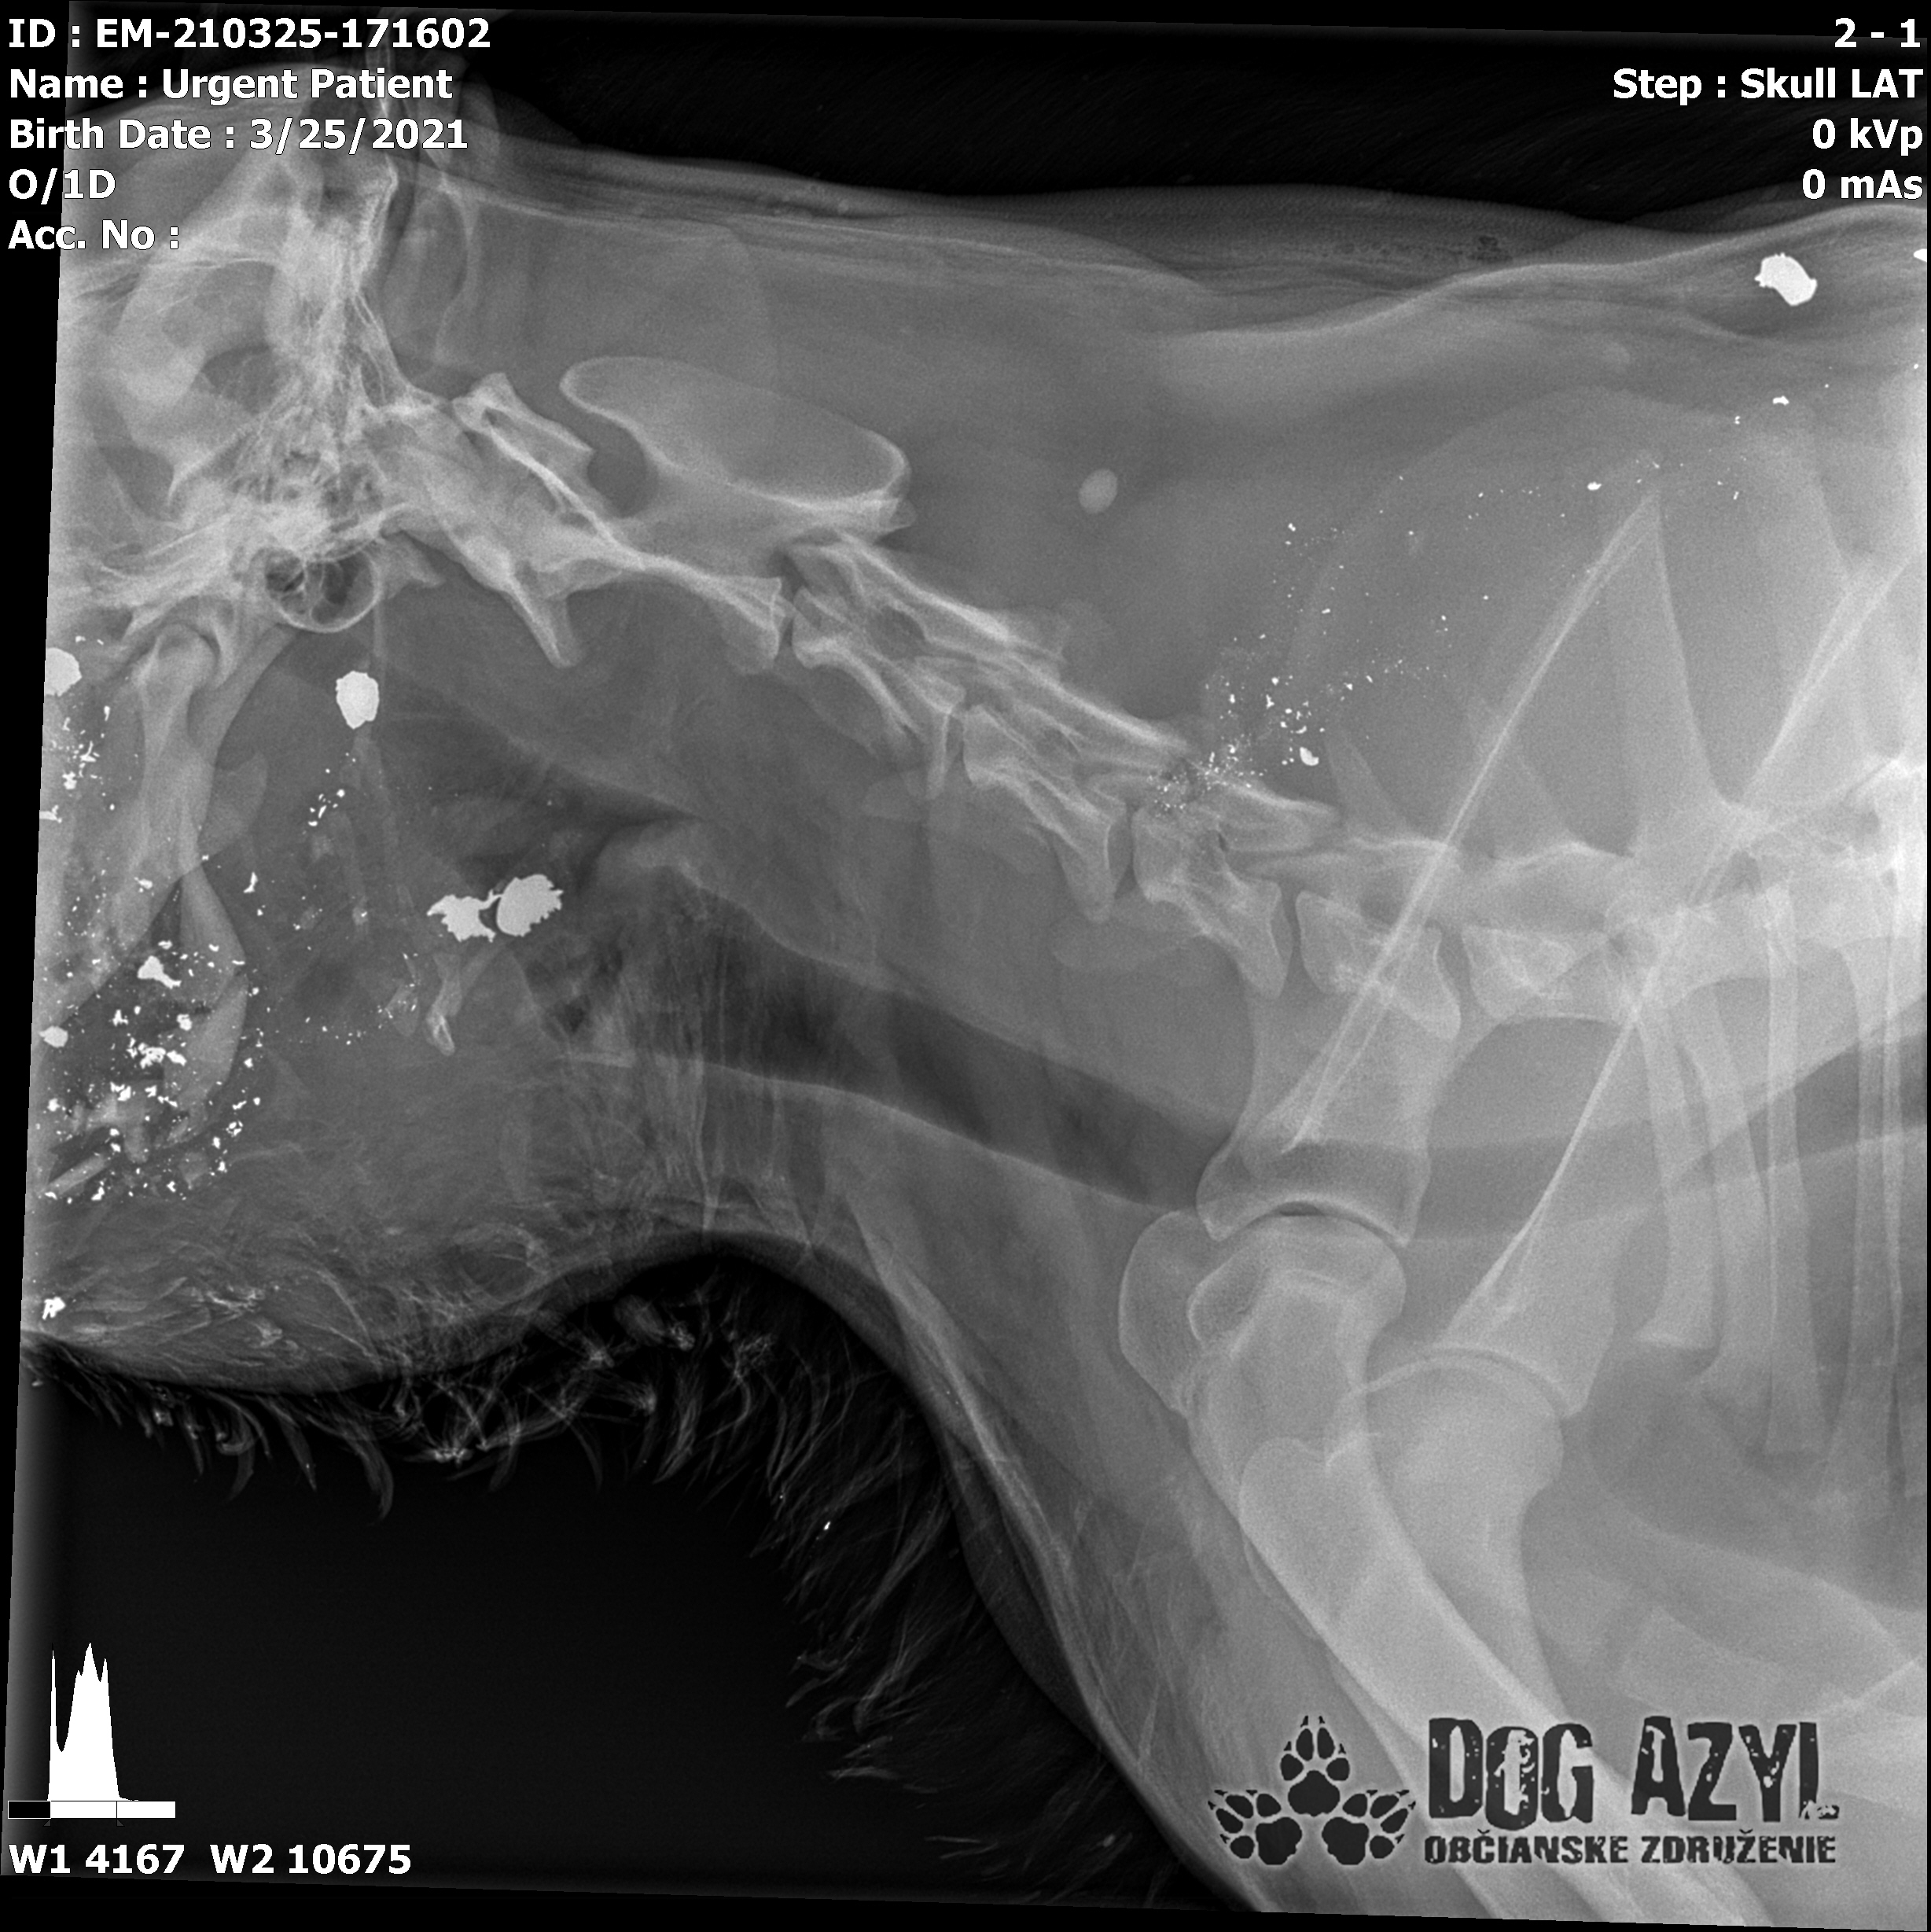

Strela zasiahla Barisa v oblasti lícnej kosti, ktorá mu rozdrvila sánku a následne putovala cez krk až po krčnú chrbticu. Úlomky z guľky (neviem ako sa to odborne volá) sa roztrieštili na "milión" kusov počas svojej cesty. Tieto úlomky sú všade (ako vidieť aj na RTG). Jeden (alebo niekoľko týchto úlomkov) sa dostali až po miechu, ale našťastie ju neprerazili. Toto spôsobilo, že Baris citlivosť v nohách na ľavej strane sice má, ale má poškodenú motoriku. Tieto úlomky sa z oblasti stavcov, miechy aj krku dnes odstránili, ale Barisko z ďaleka nemá vyhraté. Miecha je totiž zakrvácaná (opäť sa ospravedlňujem za nepresnosť a laickosť) a to, že ako veľmi je poškodená, alebo či jeho slabosť bola spôsobená "iba opuchom" sa ukáže cca do 24 hodín. Ak Baris nedajbože do zajtra stratí citlivosť v nohách, tak.. žiaľ... Ale! ak citlivosť zostane, prípadne nastane aj zlepšenie, tak vzplanie plamienok ďalšej nádeje a bojujeme ďalej!